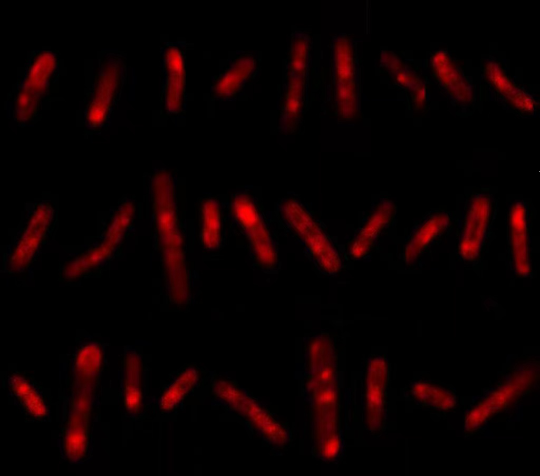

周泱介绍:“这个探针能够特异性地‘咬’住结核分枝杆菌的糖蛋白,同时它还带有一条‘尾巴’,如果糖蛋白是活性的,就代表这个结核分枝杆菌是活的,探针的‘尾巴’就会亮起荧光,灵敏度非常高?!?/p>

通过这种检测方法,医护人员在华女士的血液和尿液标本里找到了大量活的结核分枝杆菌,结合肾脏功能指标,她被确诊为肾结核,接受了为期6个月的抗结核治疗。从治疗起,华女士的症状就逐渐消失,肾脏功能指标也在好转。

已编辑图片

华女士的检测结果 亮起荧光代表有活的结核分枝杆菌